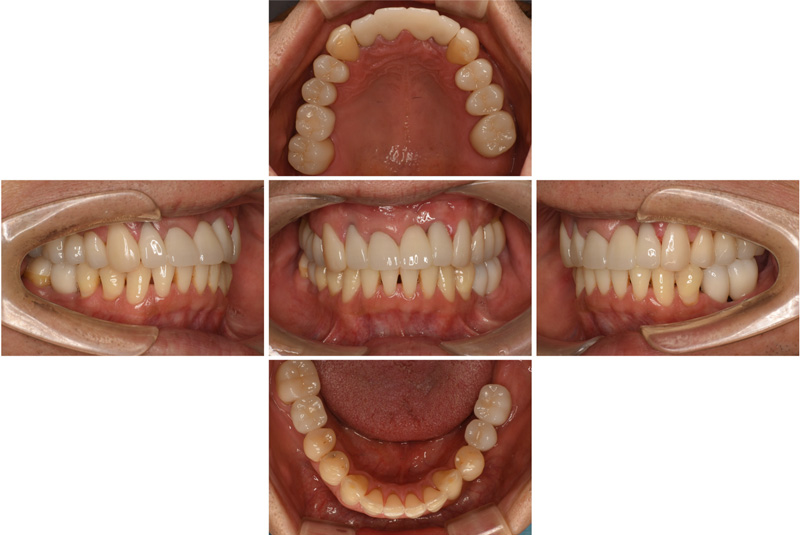

57歳男性

治療前

治療後

| 施術名 | インプラント治療 |

| 施術の説明 | インプラント治療とは、歯を抜いた所にチタン製の人工歯根を埋入し、新しく歯を入れる方法です。 |

| 施術の副作用 (リスク) | 腫れや疼痛を感じる、違和感を感じるなどの症状を生じることがあります。 |

| 施術の価格 | 53万円~+消費税 |